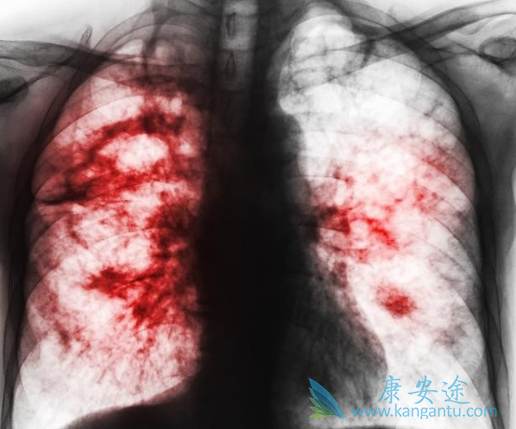

肺癌药物凯美纳主要成分是盐酸埃克替尼,服用方法是一天三次,每次1片(125mg),空腹服用或与食物一起服用,高热量食物可明显增加药物的吸收。同其它靶向药一样,凯美纳治疗期间,患者也需要根据具体情况对剂量进行调整,那一般情况剂量调整标准是什么呢?剂量调整主要是患者不良反应不耐受时剂量调整。

目前尚无针对特殊人群包括老年、儿童、孕妇或肝、肾功能不全患者的临床研究结果。对在不同年龄和性别等患者血药浓度资料分析结果显示患者的血药浓度不受年龄和性别等因素的影响,故不推荐根据年龄和性别调整凯美纳剂量。凯美纳的安全性评估是基于 312例晚期NSCLC患者的研究数据,常见不良反应为皮疹、腹泻和氨基转移酶升高,绝大多数为I~II级,一般见于服药后1-3周内,通常是可逆性的,无需特殊处理,可自行消失。